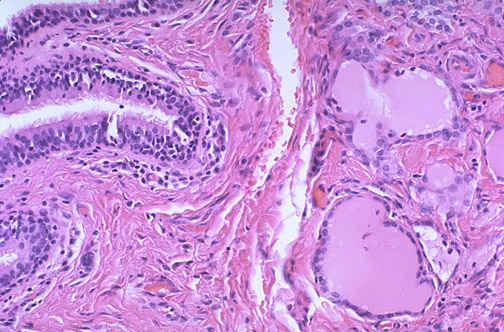

Image 6.3

Here is the microscopic appearance of the lesion. What tissues are present?.